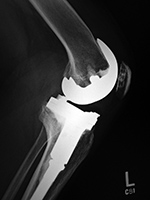

Left knee cruciate substituting revision total knee prosthesis   Cruciate substituting total knee prosthesis and patellar resurfacing.

Left knee cruciate substituting revision knee arthroplasty Left knee cruciate substituting revision total knee arthroplasty Cruciate substituting knee prosthesis - AP view Cruciate substituting knee prosthesis - latera view

46 year-old man with knee revision arthroplasty   Note the large distal femoral box. There is a surgical drain in the suprapatellar space. From Taljanovic, 2005